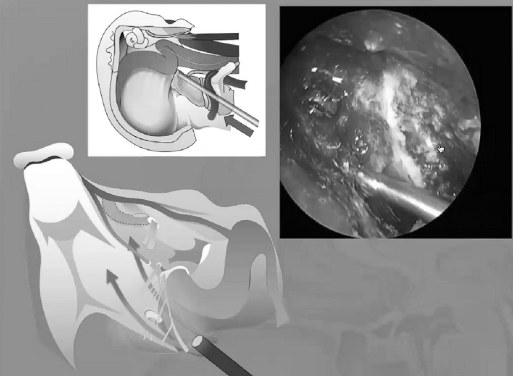

“福教授认为显微镜和内镜技术之于复杂颅底疾病,应是互补(complementary),而不是竞争(competitive)关系,更不是互斥(opposite)关系。这理念也贯彻在他每一例手术中,对于复杂复发的脊索瘤,更多的是显微镜下切除后使用各种角度内镜进行观察,对残余肿瘤的清缴。通过延长和塑形柔软的冲洗管头部,是完成筷子技术的诀窍。”

从内镜我们怎样暴露颅颈交界区,需要把后方的咽部的黏膜和肌肉移开,如果我们要往侧方走的话,这比较具有挑战性,需要切掉一半的下方的结节,我们需要切除更多的黏膜,更多的肌肉,还需要磨掉翼板的内侧,要注意颈内动脉的第二个膝部,还得切除一部分的咽鼓管,还得磨除一部分的枕髁,才能到达侧方,这样是很耗精力的。

▼这是几年前做的一个手术,先把鼻中隔先推开,然后推开那些正常的组织,这里磨掉枕髁,暴露舌下神经管。虽然很具有挑战性,但是手术做得还是不错的,我们对病人进行了长期的随访,因为我们把所有的就是切开的软组织都复位了,所以看起来还可以,经过内固定以后,病人的颅颈交界区是很稳定的。

▼下面就是我所说的有角度的器械,最后我们用脂肪来修补,我们在内镜下做缝合,在内镜下做缝合很复杂难度很大,所以很花时间,但是它是值得的。